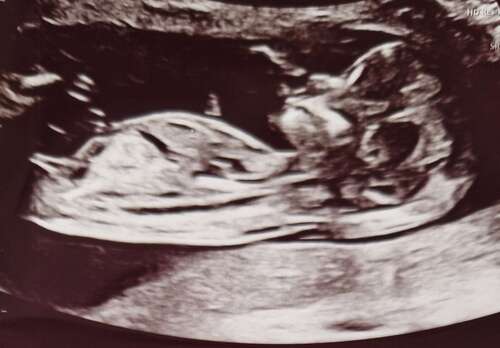

Ik zou zeggen meisje. Ik zie liggend streepje. Ik kon het met onze dochter toen goed zien op de echo van bijna 12 weken. De verloskundige wilde er toen niks over zeggen. Korte tijd later had ik een pretecho en toen dacht de echoscopiste ook aan een meisje. Dat bleek een paar weken later echt zo te zijn bij de geslachtsecho 🤗. Ik weet nog dat de echoscopiste het in haar agenda had geschreven als geheugensteuntje 😜

Jongetje hier en dat stompje was inderdaad duidelijk bij zijn nub te zien. Ook was er al iets wat op beginnende balletjes leek. Dus ik denk inderdaad ook een meisje 🙃